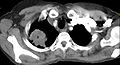

Een pancoasttumor (het hebben ervan wordt ook wel het pancoastsyndroom of sulcus-superior-syndroom genoemd) is een tumor die is gelokaliseerd in de longtop. Door de lokalisatie kan deze de werking van bepaalde zenuwen die het gelaat verzorgen in functie verstoren. Een veelvoorkomende aanleiding om hiernaar op zoek te gaan is het syndroom van Horner.